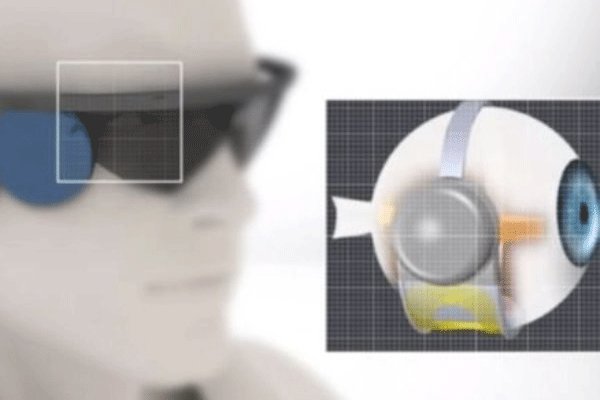

یک نابینای سوئیسی با چشم بیونیک بینا شد

محققان مرکز پزشکی لوزان سوئیس در یک عمل جراحی موفقیت آمیز توانستند بینایی یک زن سوئیسی را پس از گذشت ۱۵ سال به وی بازگردانند. این عمل جراحی می تواند امید به بینا شدن را در نابینایان زنده کرده و دنیای تاریک نابینایان را متحول کند.

در این عمل جراحی از پروتز شبکیه چشم کمک گرفته شد تا بیمار بتواند بینایی نسبی خود را بازیابد. بیمار بینایی کامل خود را به دست نیاورده اما با کمک این عمل جراحی توانست از دنیای تاریک نابینایان خارج شود.

چشم بیونیک به بیمار این اجازه را می دهد تا بتواند حاشیه و سایه اجسام روشن و تیره، تضاد رنگی، زیبایی یا تجسمی از اشیاء دور همانند تصاویری که با عینک دیده می شوند را داشته باشد.

یک نابینای سوئیسی با چشم بیونیک بینا شد

محققان مرکز پزشکی لوزان سوئیس در یک عمل جراحی موفقیت آمیز توانستند بینایی یک زن سوئیسی را پس از گذشت ۱۵ سال به وی بازگردانند. این عمل جراحی می تواند امید به بینا شدن را در نابینایان زنده کرده و دنیای تاریک نابینایان را متحول کند.

چشم بیونیک به بیمار این اجازه را می دهد تا بتواند حاشیه و سایه اجسام روشن و تیره، تضاد رنگی، زیبایی یا تجسمی از اشیاء دور همانند تصاویری که با عینک دیده می شوند را داشته باشد.